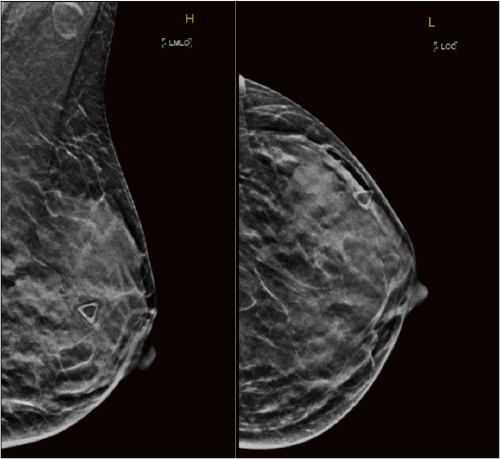

A 32-year-old female with a family history of a paternal grandmother diagnosed with breast cancer at age 65, followed by colon cancer at age 80, reported a palpable left breast mass for almost a year. Diagnostic imaging revealed a 5.2 × 1.1 × 4.3 cm heterogeneous hypoechoic mass at the left 3-to-4 o'clock position, which was suspicious for malignancy (Figure 1 and Figure 2). Subsequent bilateral breast MRI revealed a left breast 7.2 × 2.0 × 4.4 cm avid non-mass enhancement with a wedge-shaped distribution abutting the chest wall, highly suggestive of malignancy and mildly prominent left axillary lymph nodes (Figure 3).

Figure 1. Diagnostic Mammogram of Left Breast. Published with Permission